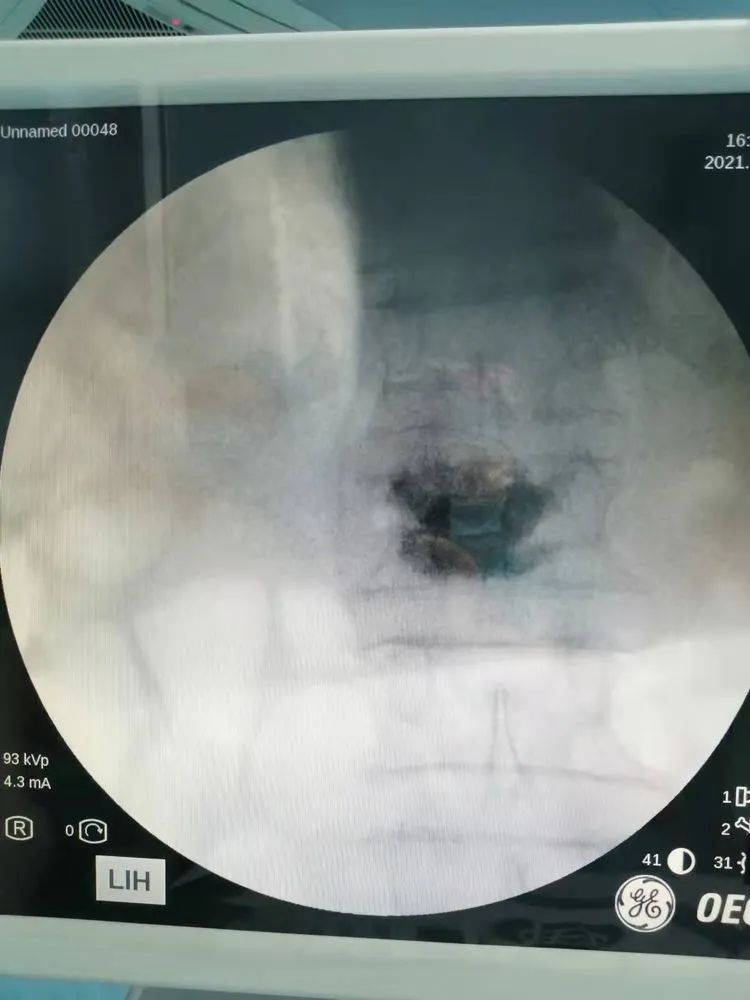

谭爷爷入住李郢孜骨科后,床位医生王丛瑞热情接待,完善检查,排除手术禁忌症,安排手术,一气呵成,9月15号下午由李清主任主刀在局部麻醉下完成“压缩性骨折椎体成形术” 。

椎体成形术是已经开展了将近50年的一个手术,具有安全、疗效明确以及明显缩短患者住院周期、降低患者临床医疗费用的一些优势。椎体成形术在影像学引导下经皮穿刺置入球囊或者骨水泥注入椎体内,可使病变椎体强化和稳定,恢复其负重功能,迅速缓解患者疼痛。

手术时间短,止痛效果明显,可进行椎体重建,对高龄患者全身干扰比较轻,安全性较高,术后恢复较快,并且并发症少,住院时间很短,可以及时缓解疼痛,避免服用药物的一些毒副作用及依赖性,可以防止椎体进一步的受压和变形,或者进一步受压之后产生脊髓压迫,可以防止进一步的损害,还可以杀死一部分肿瘤细胞。东方医院集团的专家们经过长时间地开展这项技术,基本手术时间大概15-30分钟之内就可以完成,术后患者即刻就会疼痛缓解。